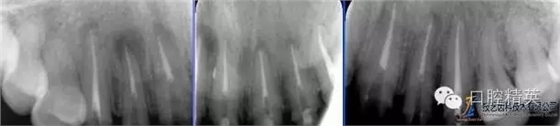

術(shù)前全景片

術(shù)前根尖片

術(shù)后根尖片